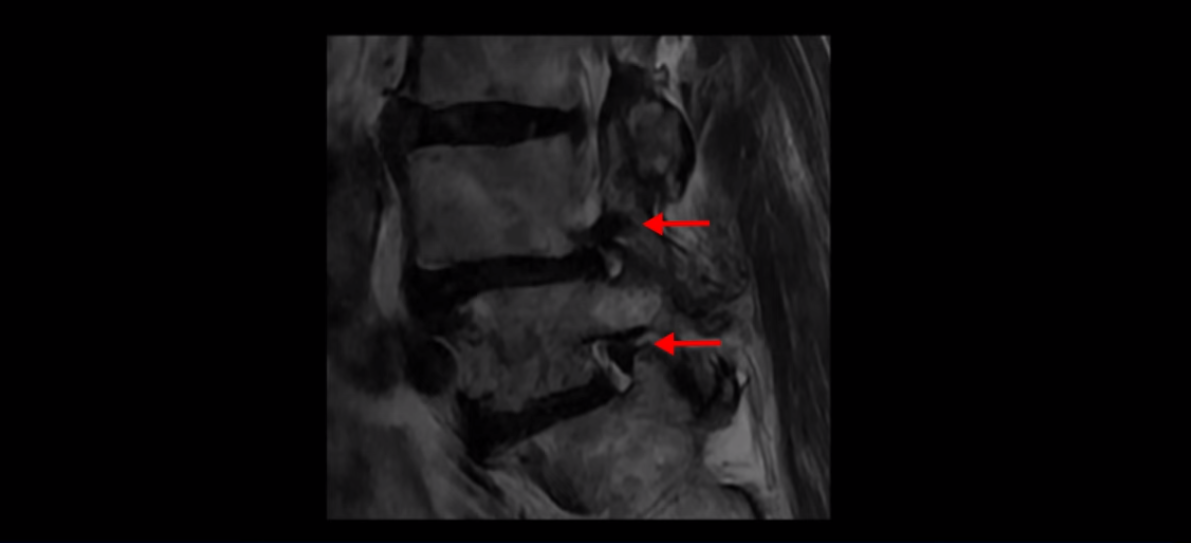

4번 5번 마디를 자세히 보면 심한 중심성 협착이 있어서 신경 구멍이 매우 좁아져 있습니다.

또 신경 가지가 빠져나가는 추간공도 매우 좁아져 있습니다.

그래서 양쪽 엉덩이가 아프고 다리는 발바닥까지 저리고 아프면서 발을 줄로 묶어놓은 것 같고 다리의 힘도 빠져 걷기가 어렵습니다.